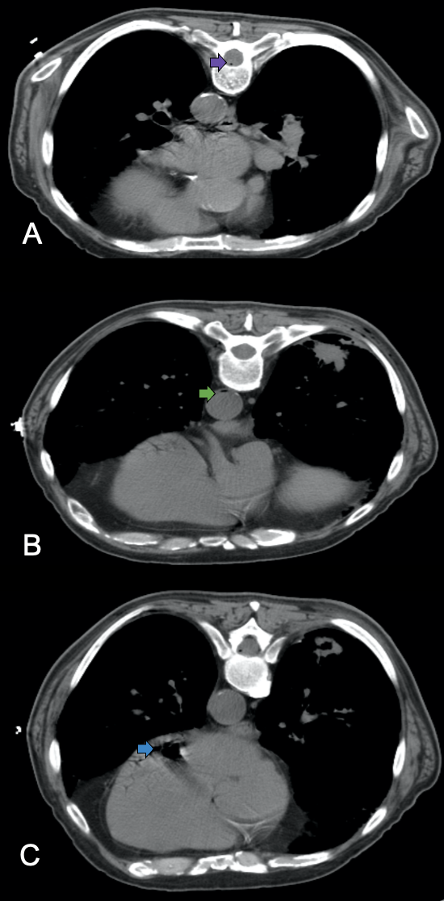

Additionally, CT imaging demonstrated air within the anterior spinal canal (Figure 3A), the descending thoracic aorta (Figure 3B), and the left ventricle of the heart (Figure 3C). Minute amounts of air were also noted in the left subcostal vessels. A CT scan of the brain showed no evidence of air emboli in the cerebral vasculature or intracranial hemorrhage.

Figure 3. (A) Axial CT demonstrates a small air bubble in the anterior spinal canal (purple arrow), indicative of air in the anterior spinal artery. (B) Axial CT shows air bubbles in the descending thoracic aorta (green arrow). (C) CT reveals an anti-dependent air pocket within the left ventricle of the heart (blue arrow).